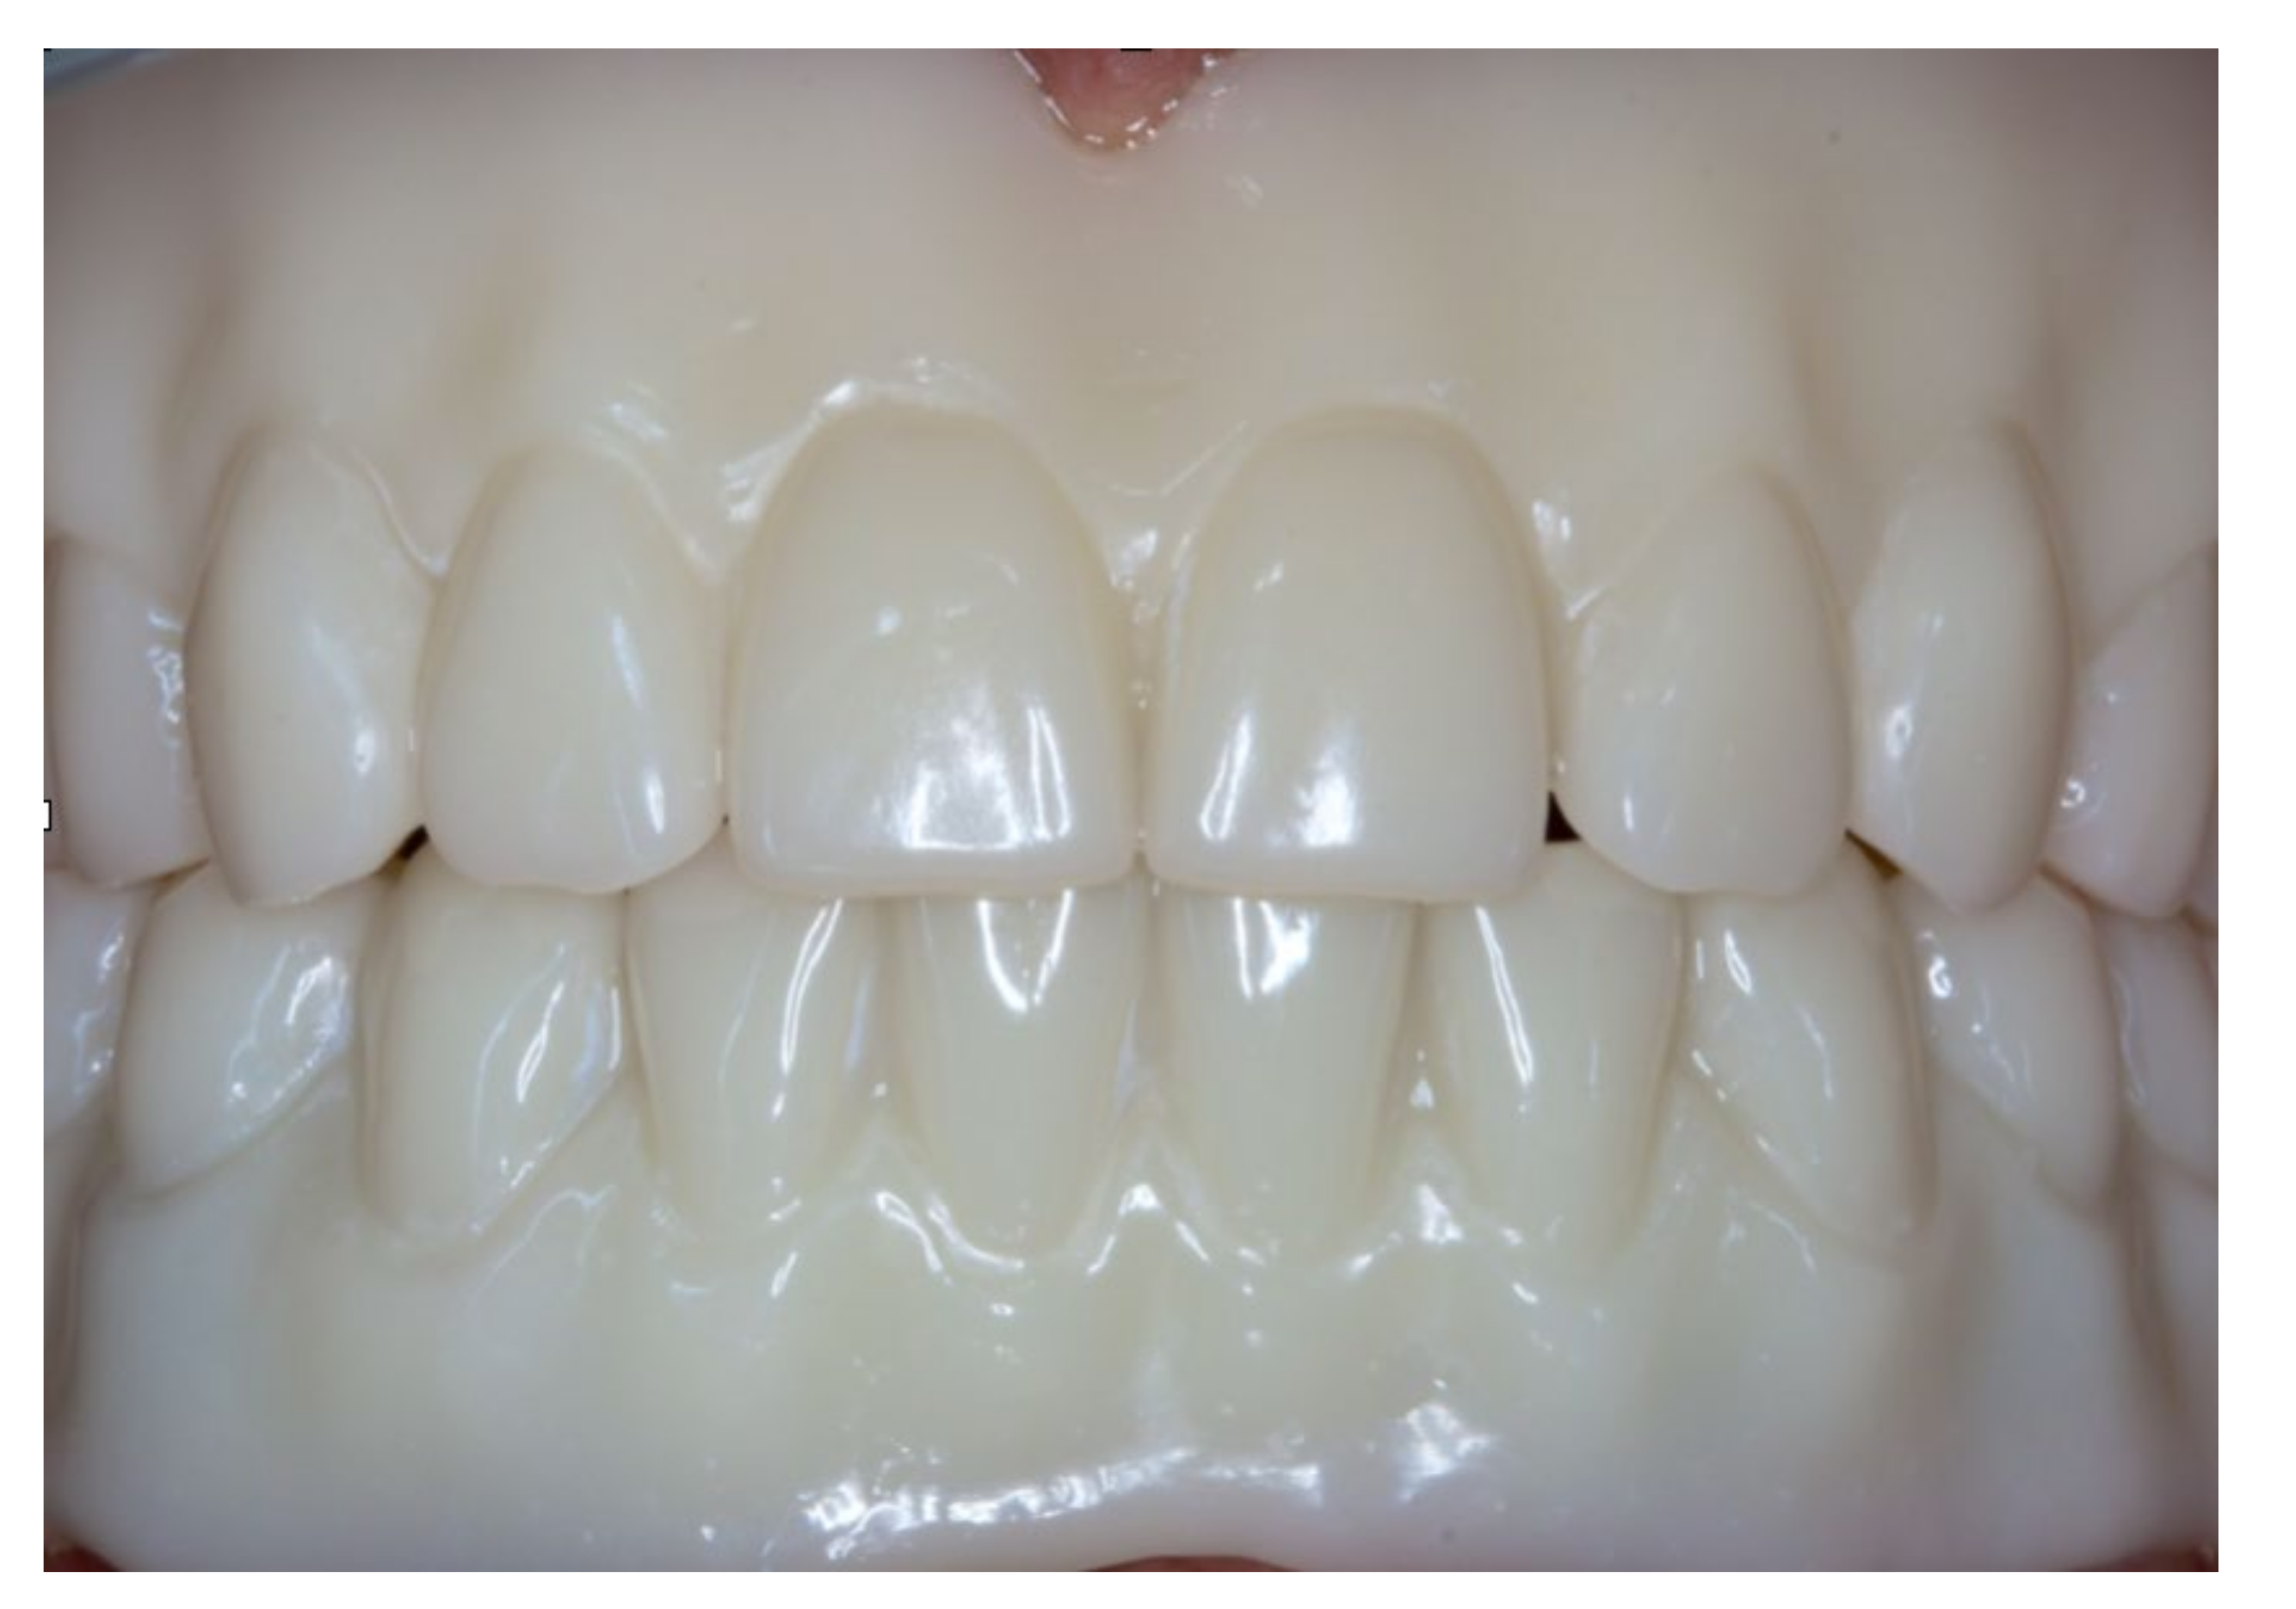

Figure 20.

Inserted complete denture in the upper jaw.